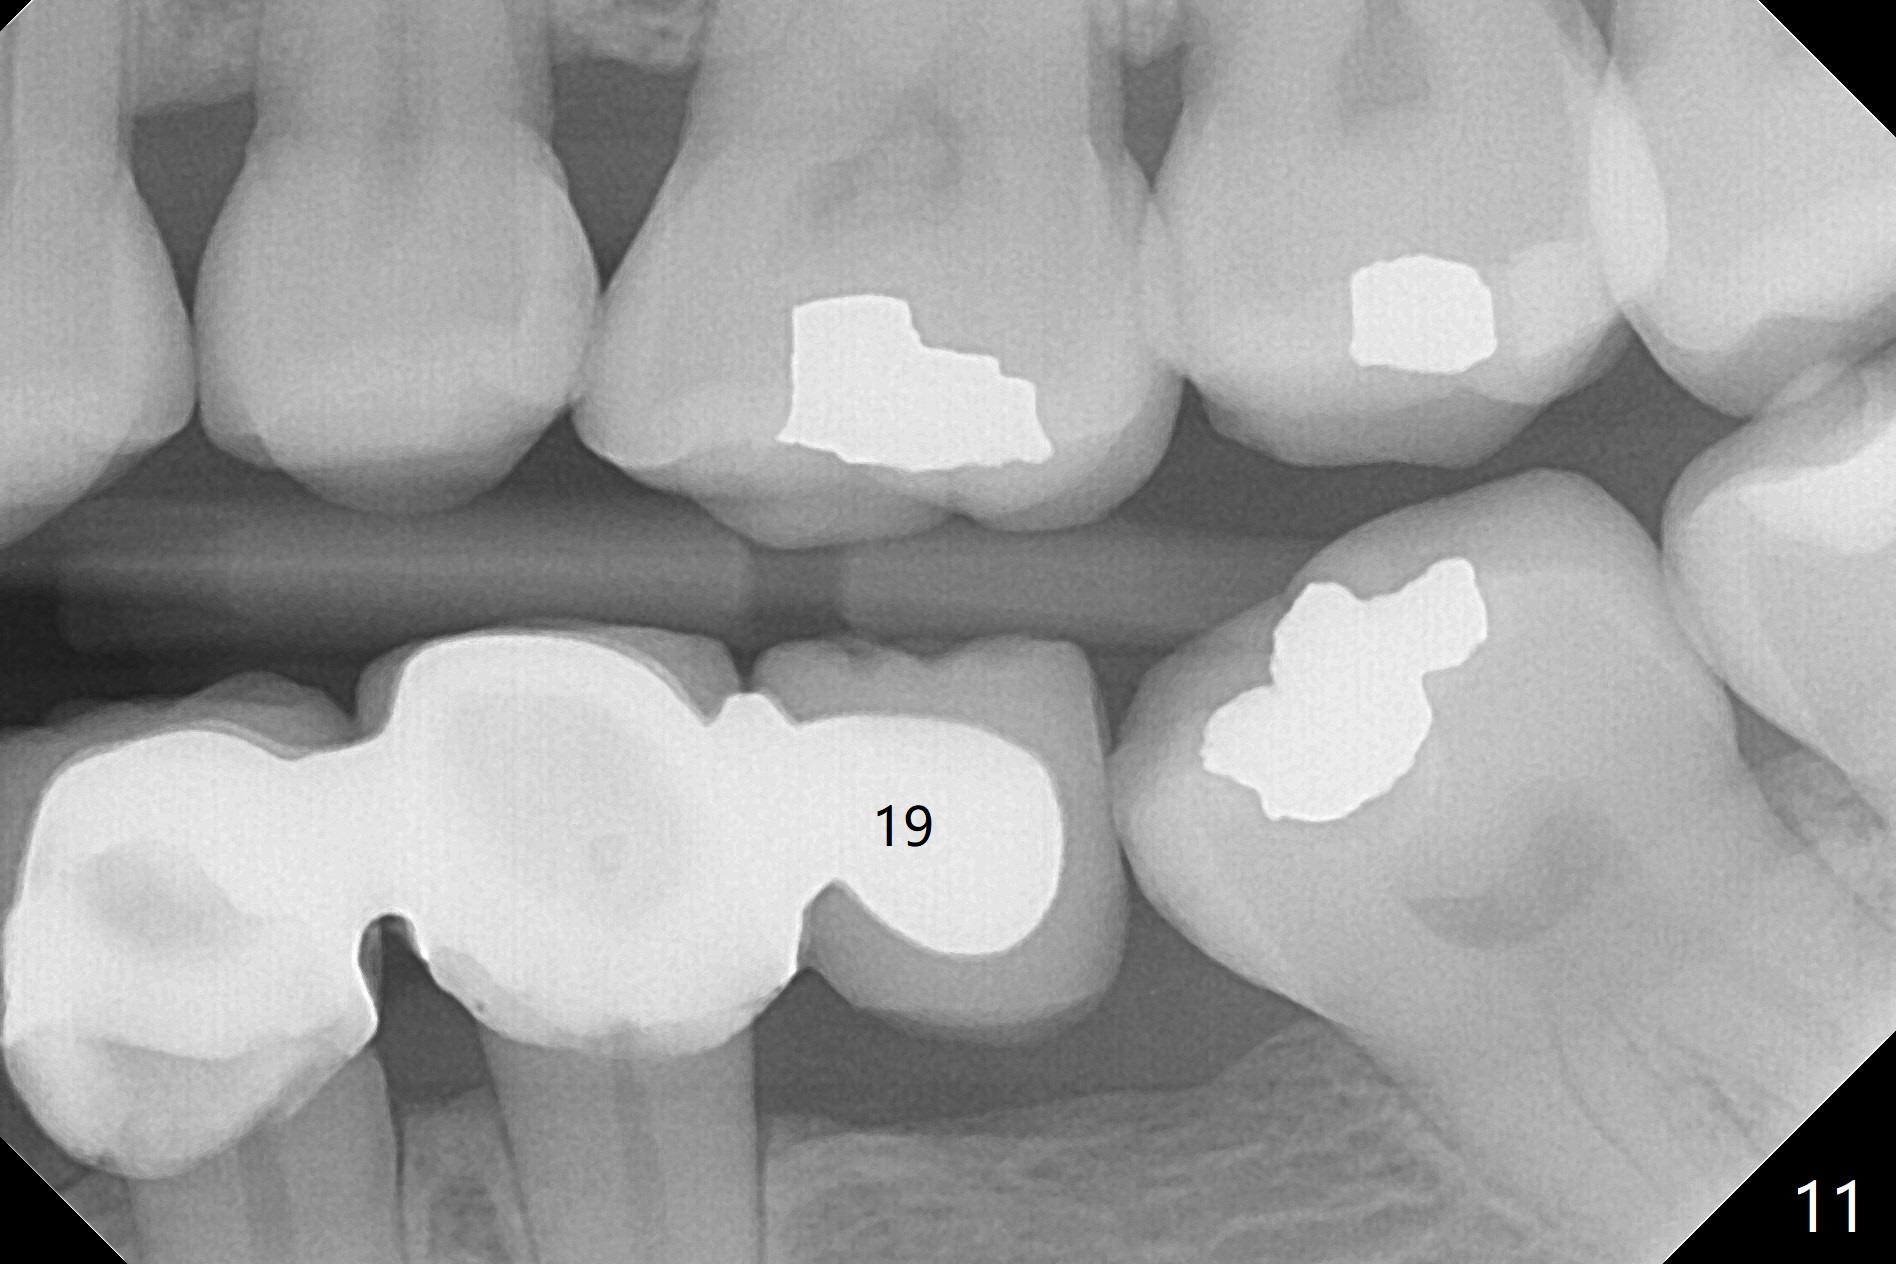

The patient returns for final restoration 3 months postop; bone resorption around the 1-piece implant is minimal (Fig.7). The definitive restoration is also splinted. The latter is further justified when the implant at #30 is found to be distal prior to cementation (Fig.8 *). It appears that implant spacing at the root level is more critical than parallelism, as compared to Fig.7. Let us improve this aspect. Bone loss around the implants remains minimal 7 months post cementation (Fig.9). It is the same 1 year 8 months post cementation (Fig.10), as compared to a cantilever FPD on the other side (Fig.11). The bone density around the implants at #30 and 31 increases 2 year 8 months post cementation (Fig.12).